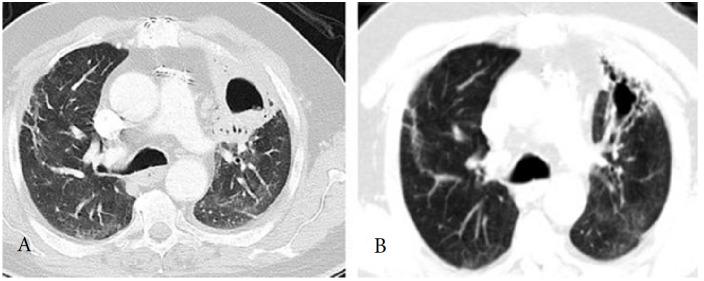

Post-COVID syndrome: pulmonary complications.

Severe acute respiratory syndrome coronavirus 2 (SARS-CoV-2) has infected millions of people worlwide and caused a pandemic that is still ongoing. The virus can cause a disease named as COVID-19, which is composed of multi systemic manifestations with a pulmonary system predominance. As the time passes, we are dealing more and more with a wide variety of effects and complications of the disease in survivors as far as with concerns about the clinical outcome and the timeline of symptoms in different patients. Since the lungs are the most involved organs and the post-COVID prolonged and persistent effects are mainly related to the pulmonary system, it is crucial to define and predict the outcome and to determine the individuals that can progress to fibrosis and loss of function of lungs. This review summarizes the current literature regarding the pulmonary complications in post-COVID syndrome and the management of these conditions.